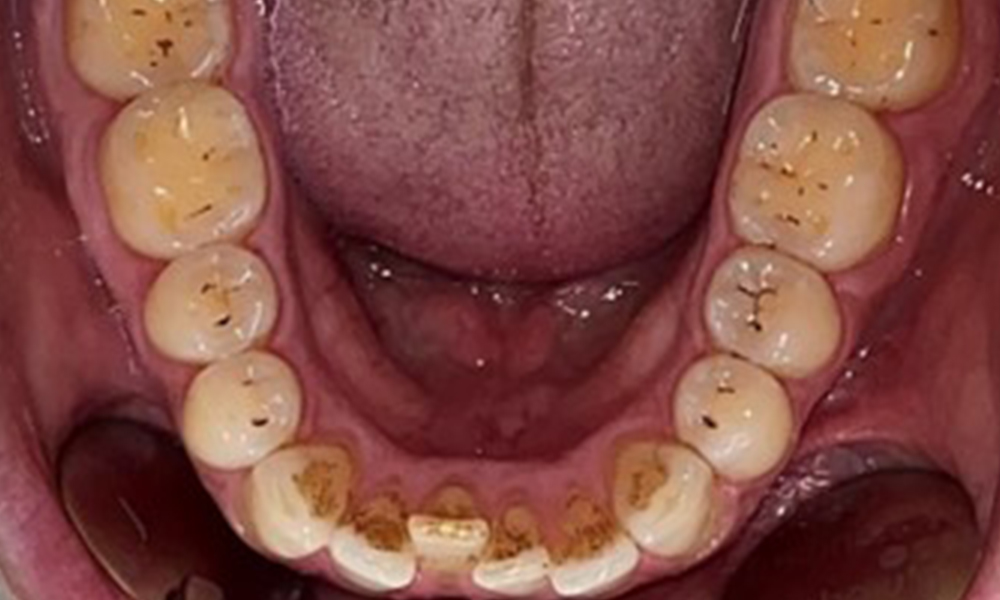

Occlusal view of the mandible.

Fig. 4: Occlusal view of the mandible, © Dr R. Krapf

The patient has full dentition with a total of 28 teeth. There were noteworthy erosions and attritions. (Fig. 4, Fig. 5). Due to bruxism, the patient has been wearing a splint with an adjusted bite block at night for many years. The erosions were caused by long-term consumption of isotonic beverages. No periodontal bone loss or active caries were observed.

Full complement of adult teeth with no caries or radiologically recognizable bone loss was observed (Fig. 6). Radiological enamel and cusp loss were particularly evident on 36 and 37.